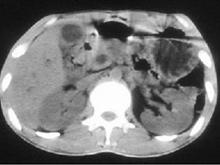

慢性胆囊炎(chronic cholecystitis)系指胆囊慢性炎症性病变,大多为慢性结石性胆囊炎,占85%~95%,少数为非结石性胆囊炎,如伤寒带菌者。本病可由急性胆囊炎反复发作迁延而来,也可慢性起病。临床表现无特异性,常见的是右上腹部或心窝部隐痛,食后饱胀不适,嗳气,进食油腻食物后可有恶心,偶有呕吐。在老年人,可无临床症状,称无症状性胆囊炎。